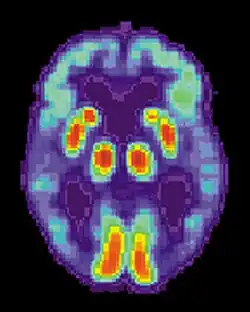

The pursuit rotor task is a simple pure visual-motor tracking test that has consistent results within age groups.[20] This displays a measurement of procedural memory as well as demonstrates the participant's fine motor skills. The pursuit rotor task tests the fine-motor skills which are controlled by the motor cortex illustrated by the green section below.

[21] The results are then calculated by the participant's time-on and time-off the object. Amnesic participants show no impairment in this motor task when tested at later trials. It does however seem to be affected by lack of sleep and drug use.[22]